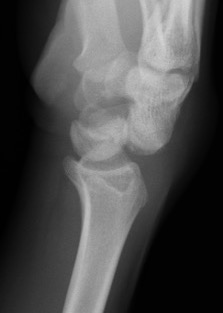

AP X-ray

Disruption of Gilula's 3 smooth carpal arcs / triangular lunate

Normal versus disruputed Gilula's carpal arcs

Piece of pie / triangular appearance of lunate

Lateral xray

Distal radius / lunate / capitate: not aligned, spilled teacup

Normal versus spilled tea cup appearance on lateral with spilled tea cup